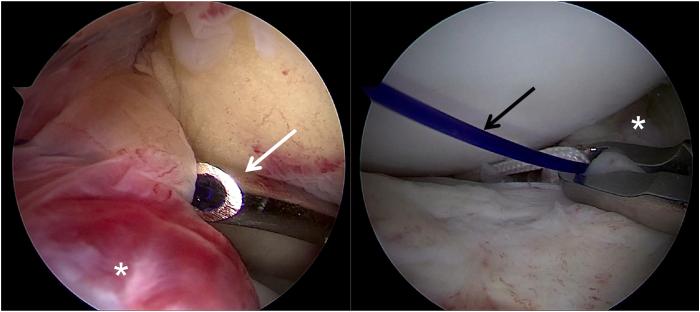

Few cases of anterior cruciate ligament (ACL) tibial avulsion injuries occur in adolescents. Bony ACL avulsion from the tibial side has been treated by various methods ranging from conservative management to a wide range of operative procedures. Various arthroscopic operative procedures are available to reduce and fix these fractures. We describe a technique of arthroscopic "8" knotted fixation without any tibial tunnels for tibial-sided ACL avulsion. This simple technique avoids the potential complications of hardware fixation within a joint. It represents an arthroscopic treatment option for ACL tibial avulsion injuries.

青少年前交叉韧带(ACL)胫骨撕脱伤的病例很少见。从保守治疗到广泛的手术操作,胫骨侧ACL骨撕脱伤有多种治疗方法。有多种关节镜手术可用于复位和固定这些骨折。我们描述了一种关节镜下“8”字打结固定技术,用于胫骨侧ACL撕脱伤,无需任何胫骨隧道。这种简单的技术避免了关节内硬件固定的潜在并发症。它代表了一种治疗ACL胫骨撕脱伤的关节镜治疗选择。